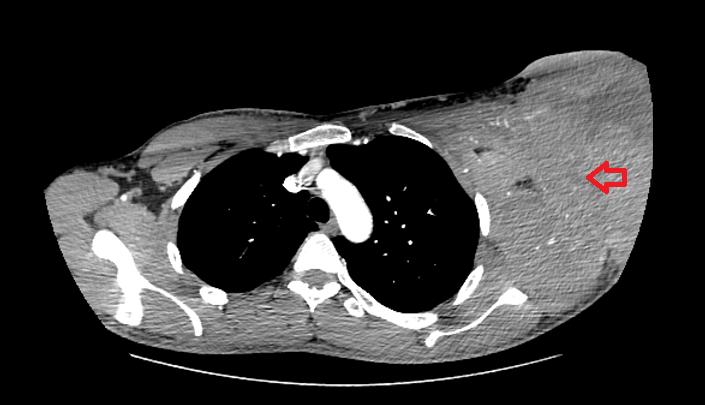

患者CT图像,红色箭头所指为左侧腋窝巨大包块所在区域